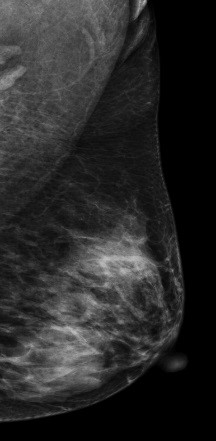

DBT图像:

影像描述: 常规2D图像MLO位左乳腺内见多个小结节影,下象限似见一团块影,边界模糊,CC位上并没有发现异常团块影,在V-Perview图像MLO位下象限见一类圆形团块影,部分边界尚清,但CC位上并没发现明显异常团块影,DBT断层图像在MLO和CC位上左乳内下象限清晰可见类圆形致密影,其边缘光滑锐利。 影像诊断: 左侧乳腺多发良性结节,BI-RADS 3。 病例点评: 最后病理证实纤维腺瘤,类似这样病例DBT可以给我们提供更多诊断信息有助于明确病变性质。